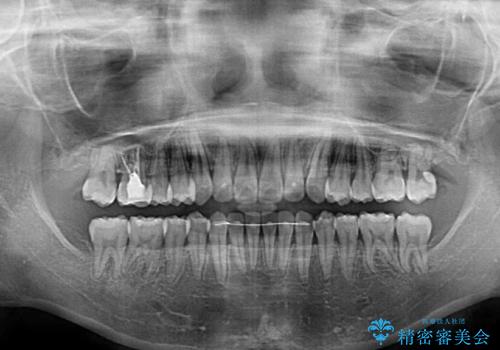

1日22時間の装着時間をしっかり守ってくださったので、予定していた1年よりも早く治療を終えることができました。

インビザライン矯正特有の奥歯がしっかりと咬合しない感覚も改善され、大変満足していただきました。